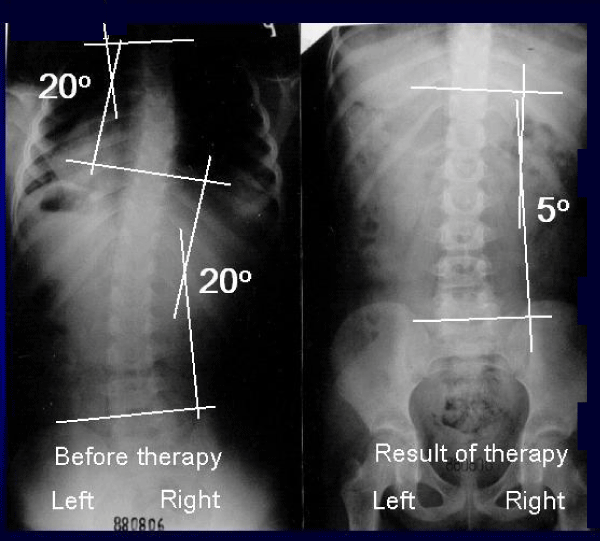

图9:安娜,12岁。880806年的历史。脊柱侧凸S型2nd/B epg组和类型。2年零6个月的新疗法。(1)只用左腿“轻松地”站立,(2)每天多次向前和向左侧弯曲练习,(3)在学校进行运动,外加空手道,(4)以胚胎姿势休息和睡觉。